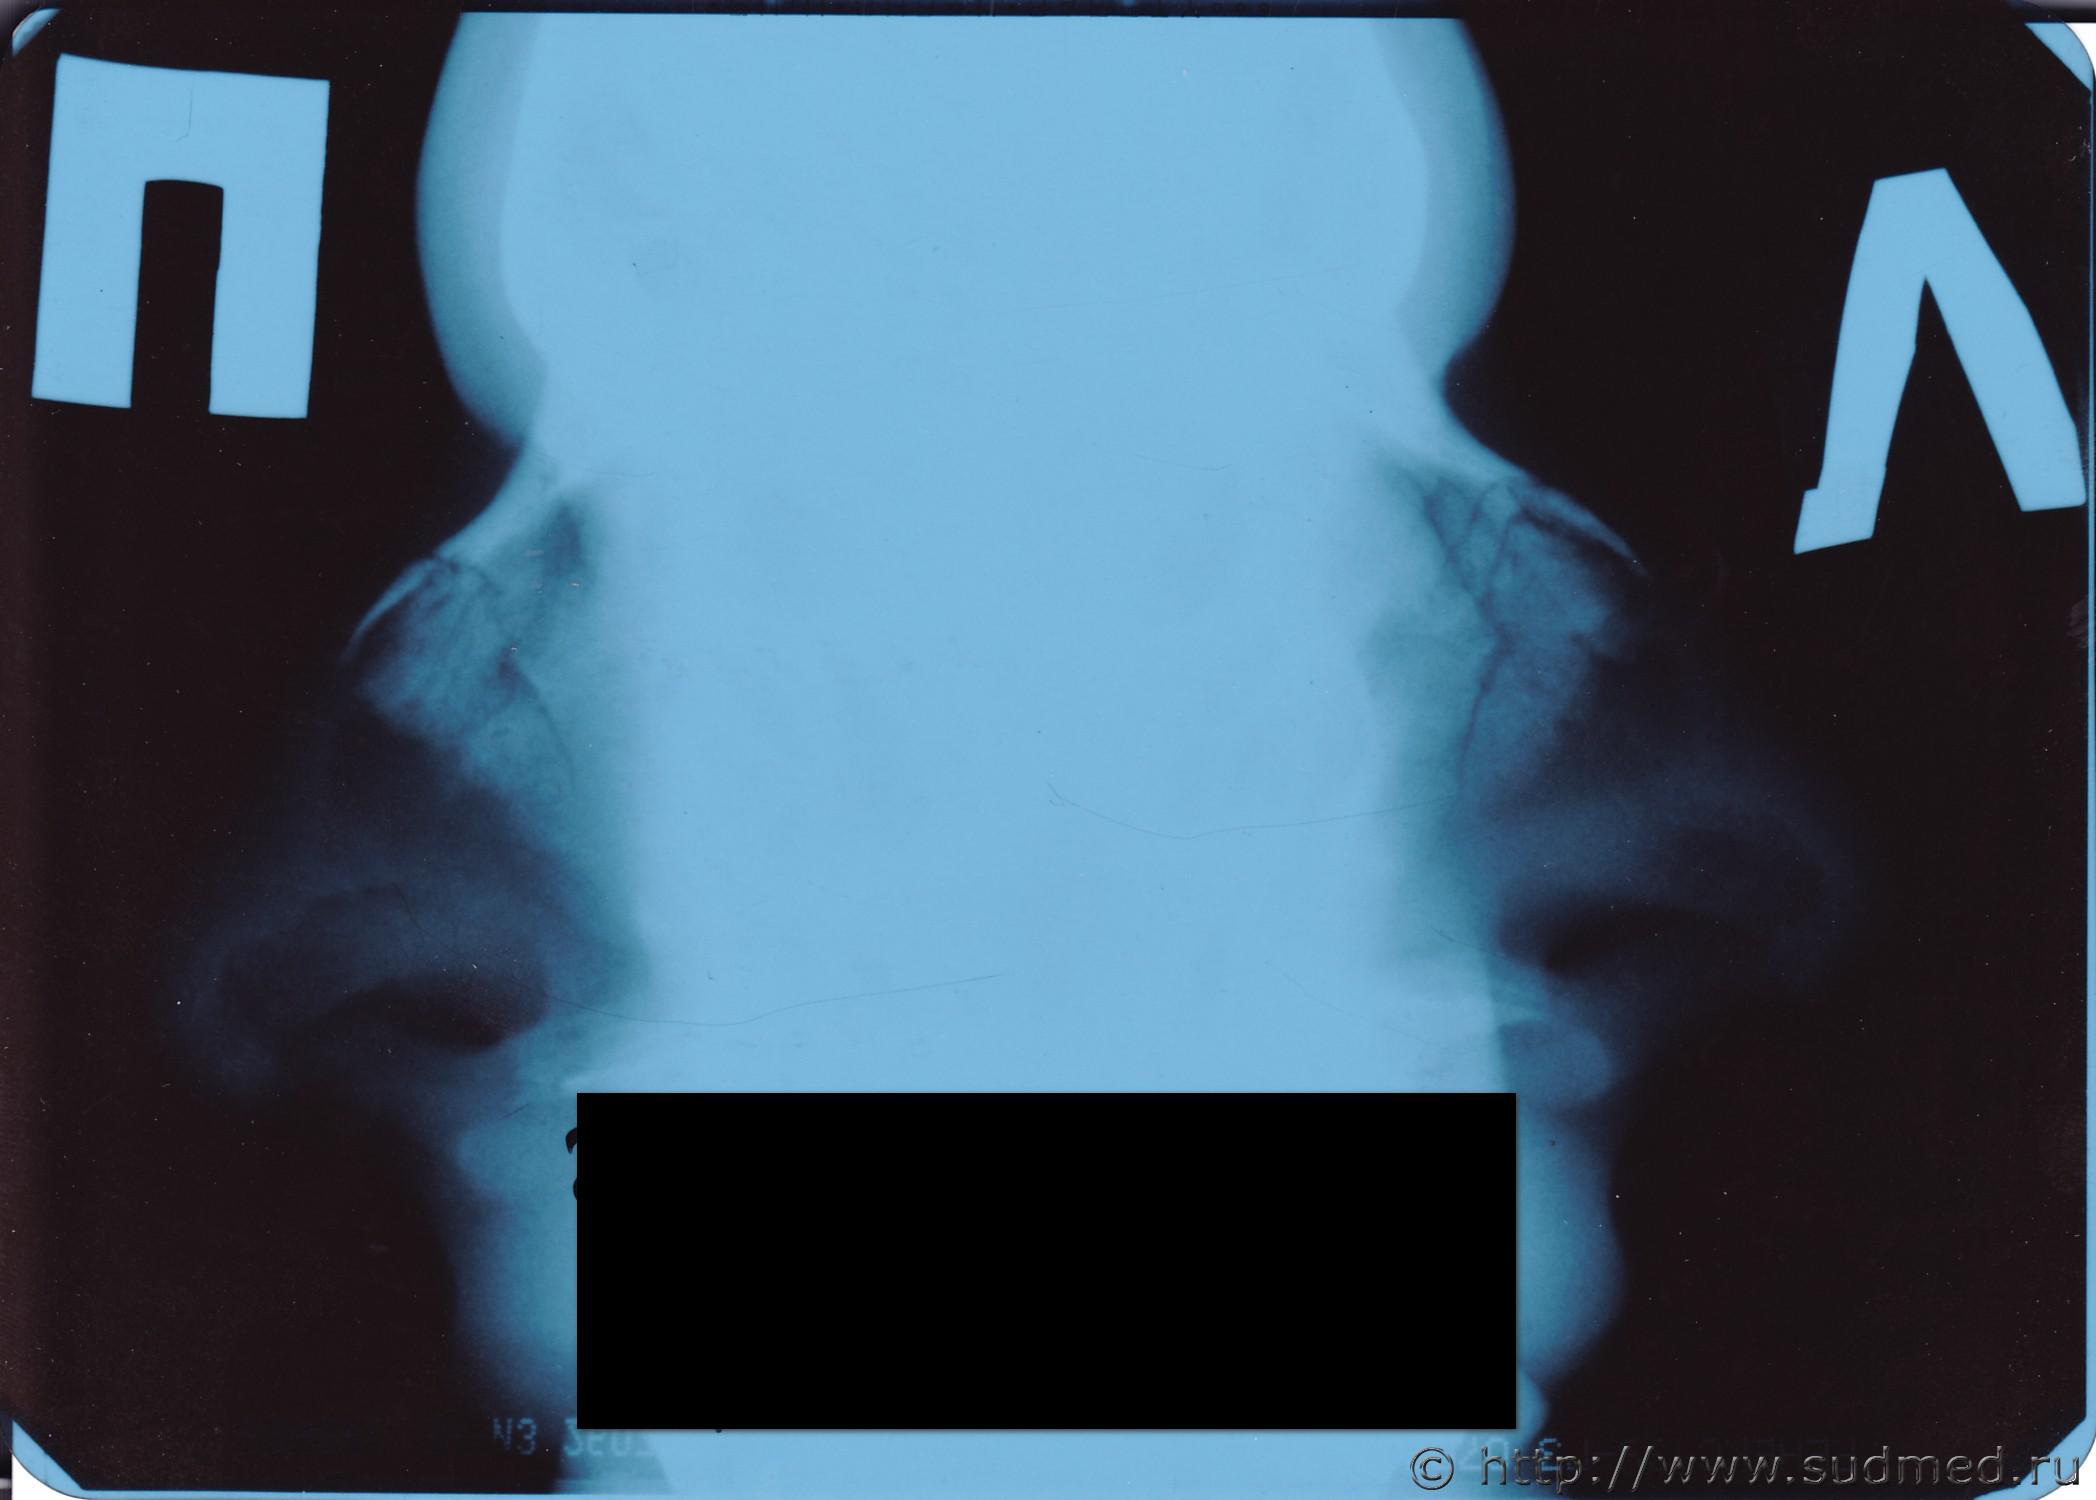

Рентген переломов носа + описание снимков.

Это не перелом - а отрыв хрящевой части от костной (снимок очень жесткий).

И вроде рентгенолог пишет о переломах костей носа, а не хрящей.

Но я не прав - прав рентгенолог - там переном носовых косточек. Что степени вреда не меняет.